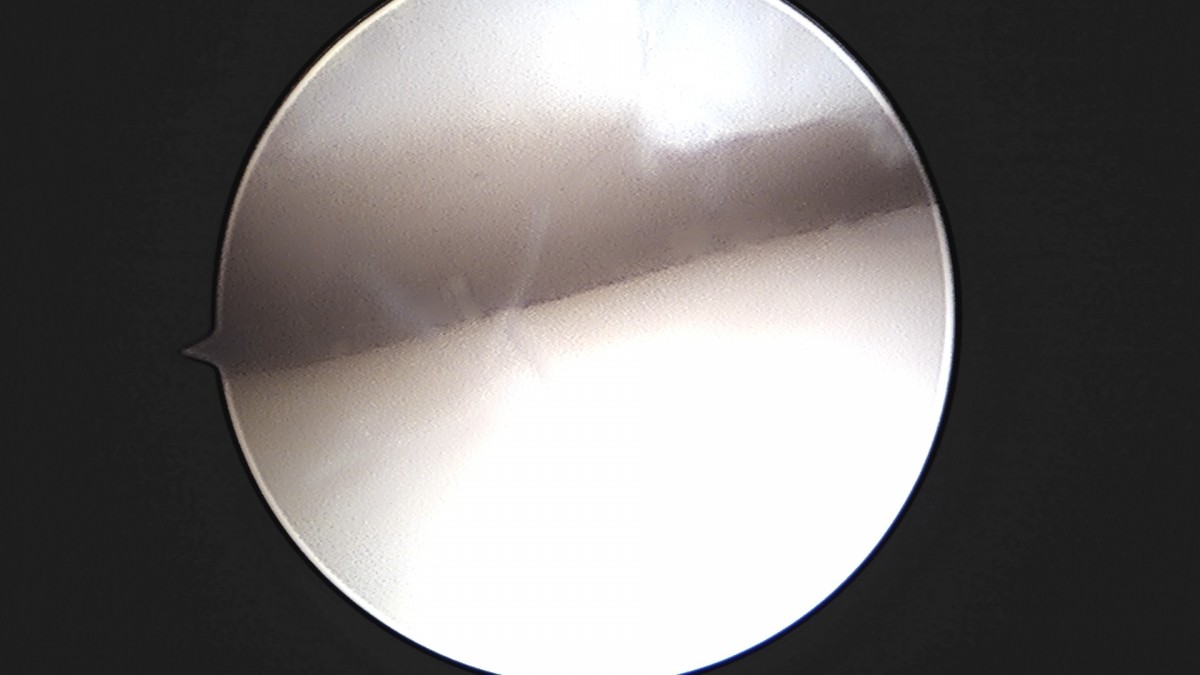

이재상원장님 발목 인대 봉합술 이지O 환자

작성자 최고관리자 댓글 0건 조회 681회 작성일 25-09-16 16:26